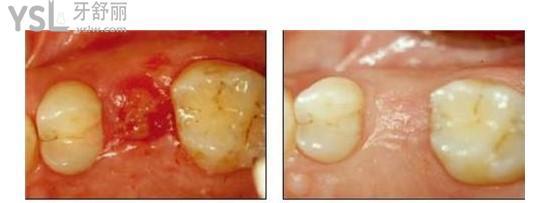

拔完牙恢复两天的样子:

▲

拔完牙恢复完成样子: